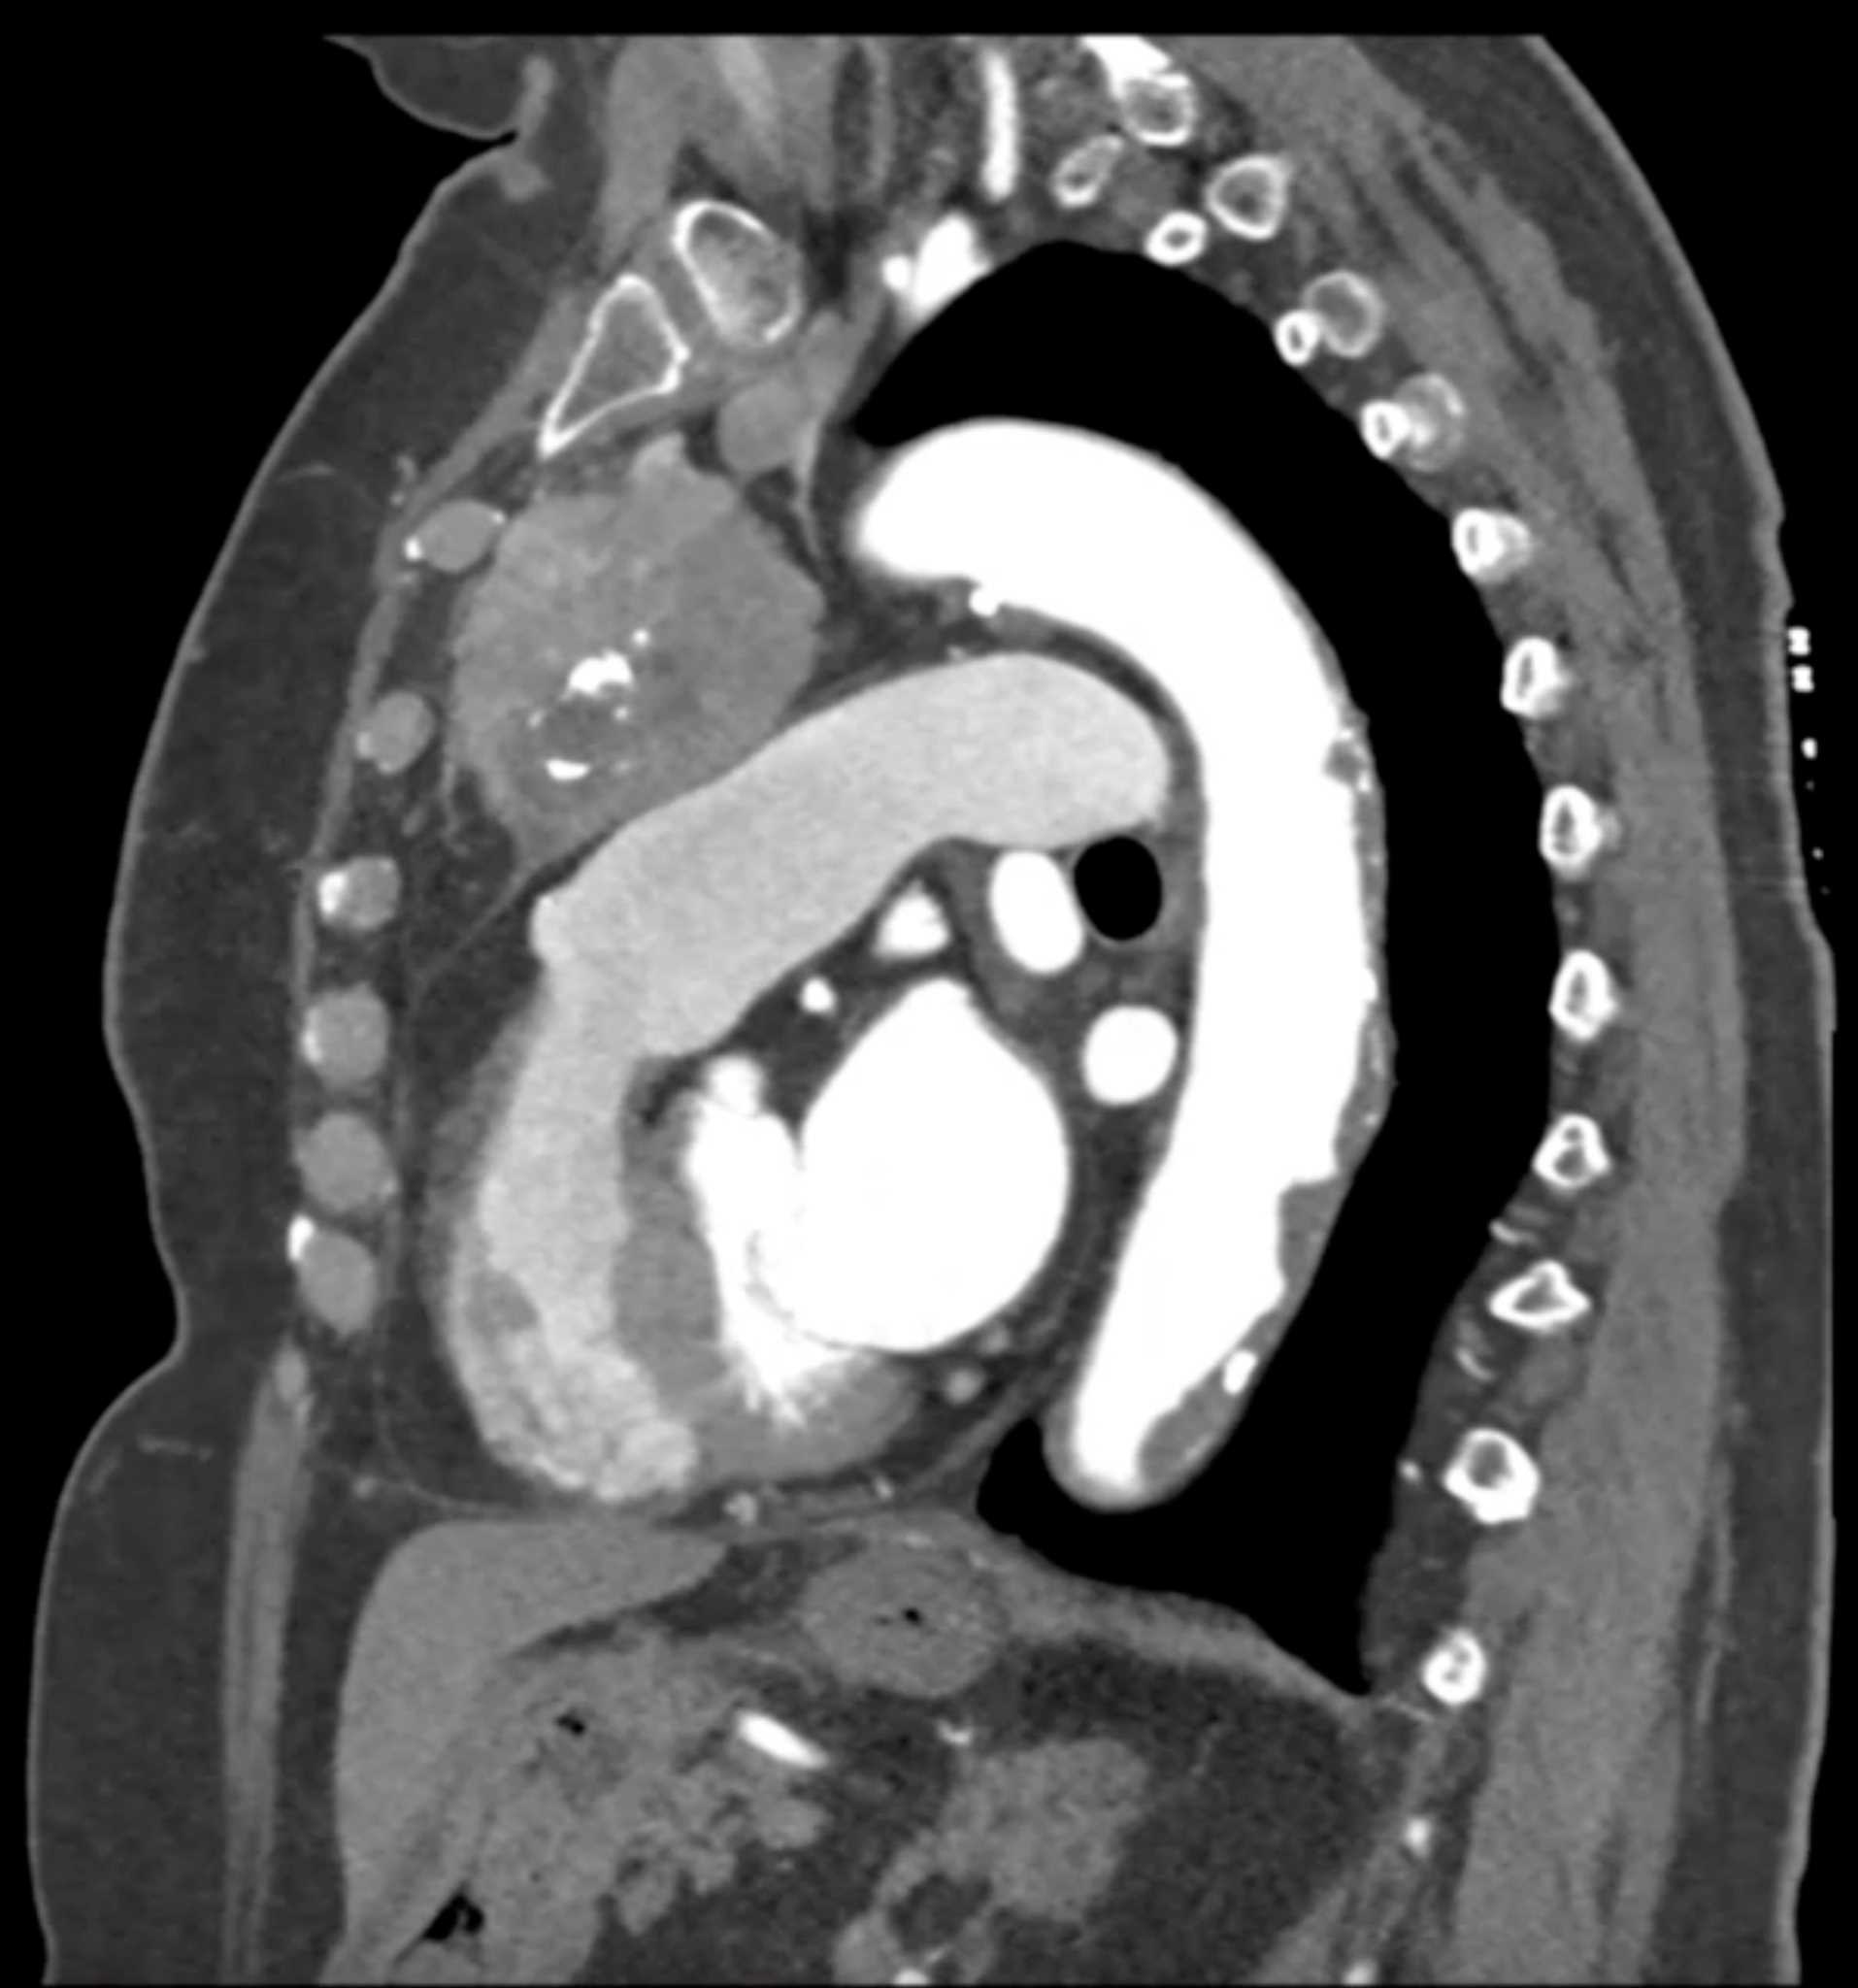

Thymic Carcinoma